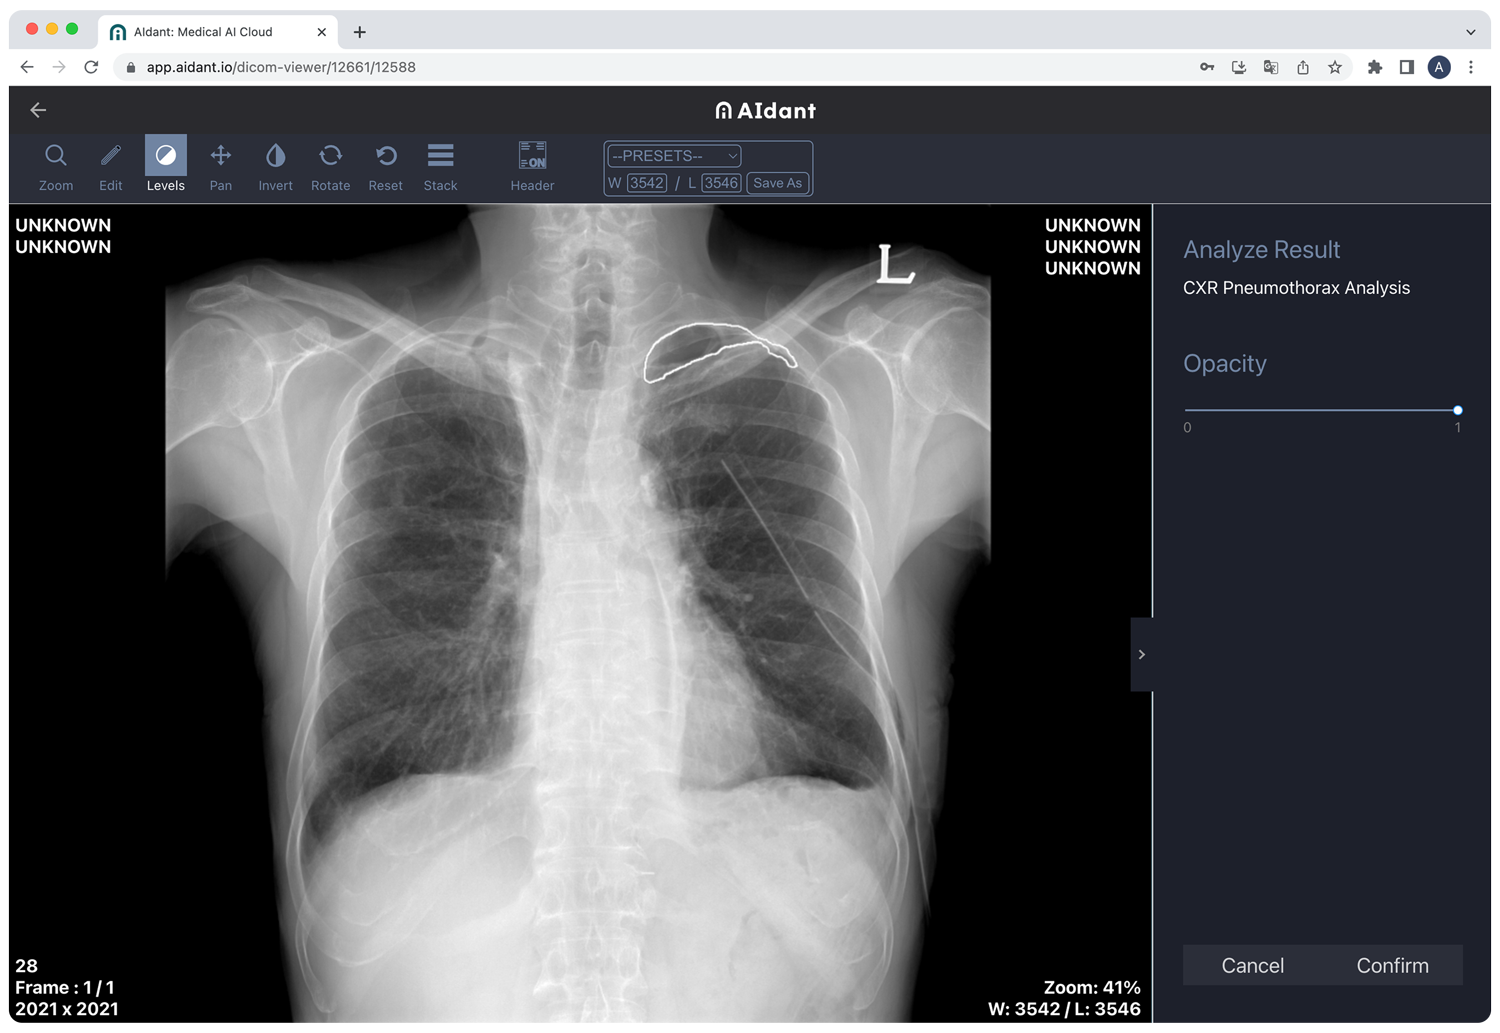

- Medical Image Analysis: CXR Pneumothorax, CXR Osteoporosis, CXR Infectious Disease, CXR Cardiothoracic Ratio, CXR Cobb Angle

AIdant enables HCPs to spend more time on patient care, by reducing time-consuming medical image analysis. By providing DICOM medical imaging viewer and AI analysis directly on a web browser, AIdant eliminates the need to install or invest in new equipment. HCPs can also share medical images and patient data with peers for second opinions and remote collaboration.